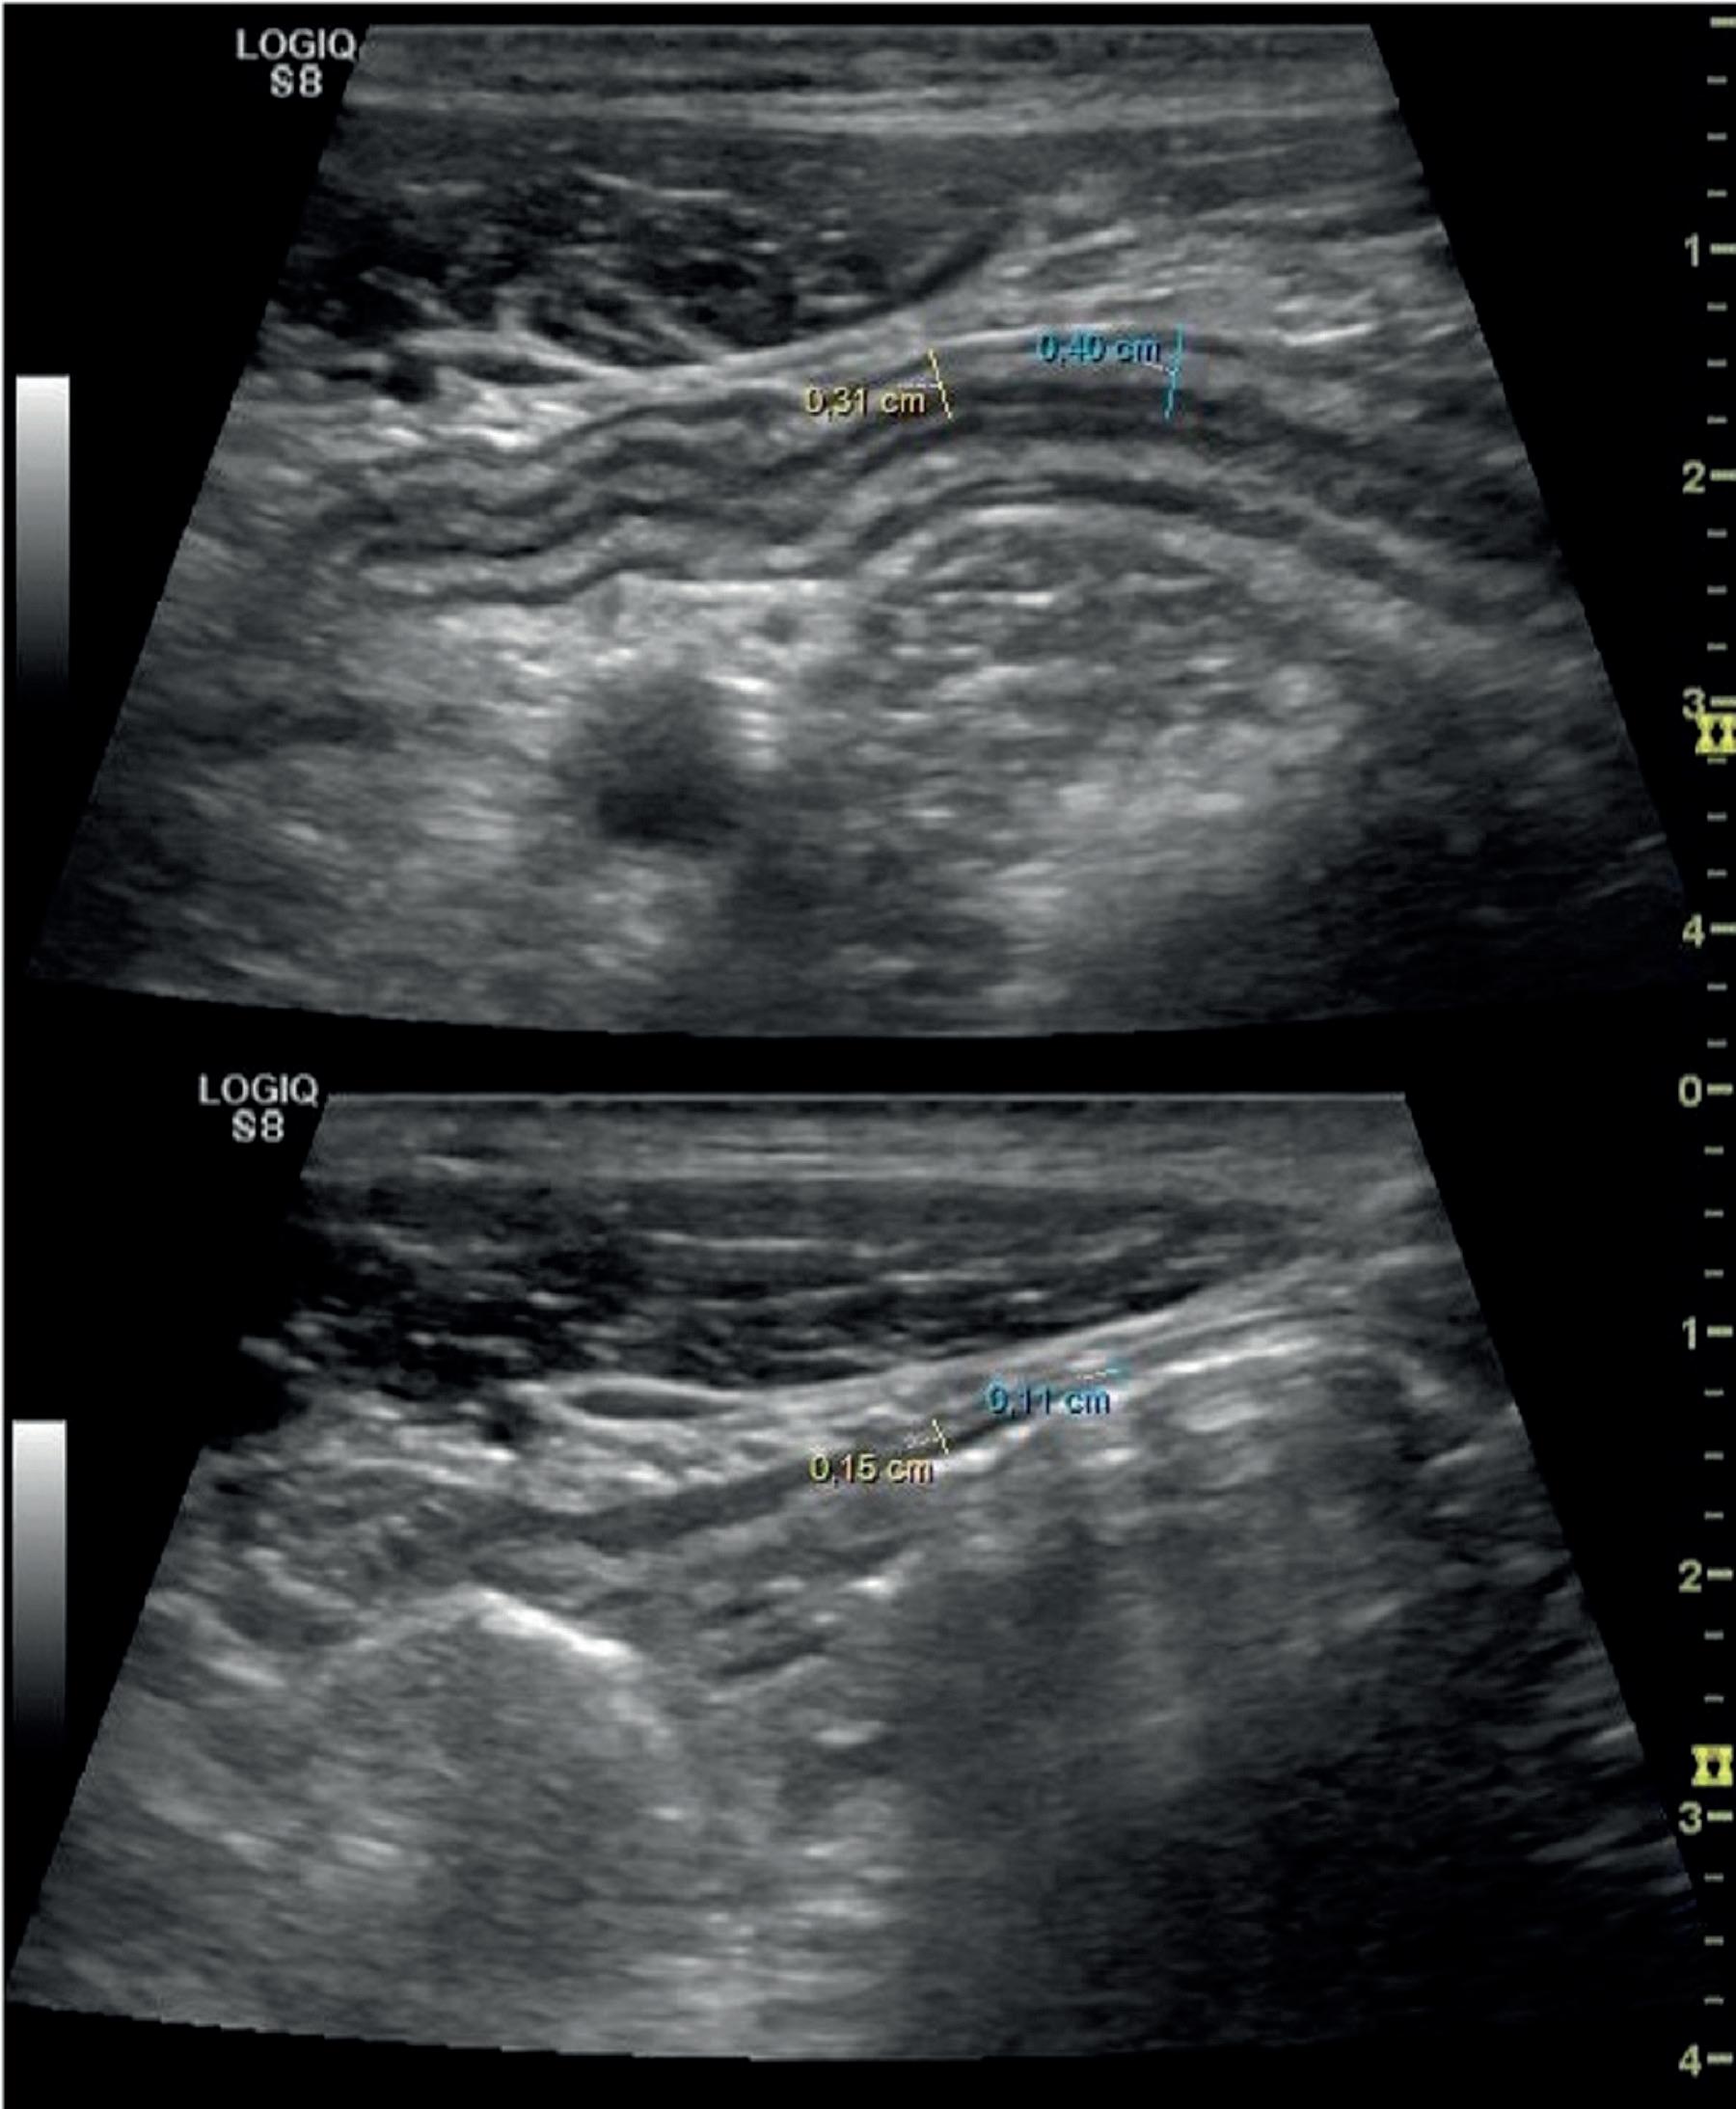

Etter dette har imidlertid interessen tatt seg opp. Noe av utfordringen med de tidlige studiene har vært at man har definert en tarmveggstykkelse på 3 mm (noen ganger 4mm) som cut-off mellom aktiv og inaktiv ulcerøs kolitt. Dette er en god cut-off til å skille mellom ingen/lett og moderat/alvorlig sykdomsaktivitet, men ikke til å skille mellom syk og frisk. I en studie fra Bots et al fra 2021 1 fant man imidlertid at man kan bruke en cut-off på 2,1 mm for å skille mellom MAYO 0 og MAYO 1-3 med en sensitivitet på 82,6 % og en spesifisitet på 93%. Det er altså mulig å skille mellom aktiv og inaktiv UC med GIUS.

For de av oss som ikke bare er interessert i en svart-hvitt-tilnærming til sykdomsaktivitet er det dessuten flere studier som indikerer at GIUS kan brukes til å registrere respons både på kort og noe lengre sikt. Ilvermark et al. undersøkte 56 pasienter med akutt alvorlig ulcerøs kolitt før oppstart med iv kortikosteroider og etter 48 ± 24 timer 2. De fant at pasienter som responderte hadde en reduksjon i veggtykkelse på 35,9% versus 4,1 % i nonrespondere. De Voogd et al. undersøkte 30 pasienter behandlet med tofacitinib for moderat til alvorlig ulcerøs kolitt og fant at endoskopiske respondere hadde en 58,3% reduksjon i veggtykkelse versus 13,4% hos non-respondere etter 12 uker 3. Samme gruppe undersøkte 51 UC-pasienter med moderat til alvorlig kolitt og behandling med ulike medikamenter, og fant en 40% reduksjon i veggtykkelse hos de med endoskopisk respons versus 4% hos de som ikke responderte 4

Det er altså flere studier som tyder på at man kan bruke GIUS og en så enkel parameter som veggtykkelse, til å finne pasienter som responderer på den medikamentelle behandlingen. En reduksjon i veggtykkelse på minst 40-60% indikerer behandlingsrespons.

Figur 1: Pasient med akutt alvorlig ulcerøs kolitt. Veggtykkelse i sigmoideum før oppstart med 100 mg hydrokortison iv x3/dag var 3,6 mm. Etter 3 dager med behandling ble veggtykkelsen redusert til 1,3 mm. Det tilsvarer en tykkelsesreduksjon på 64%.